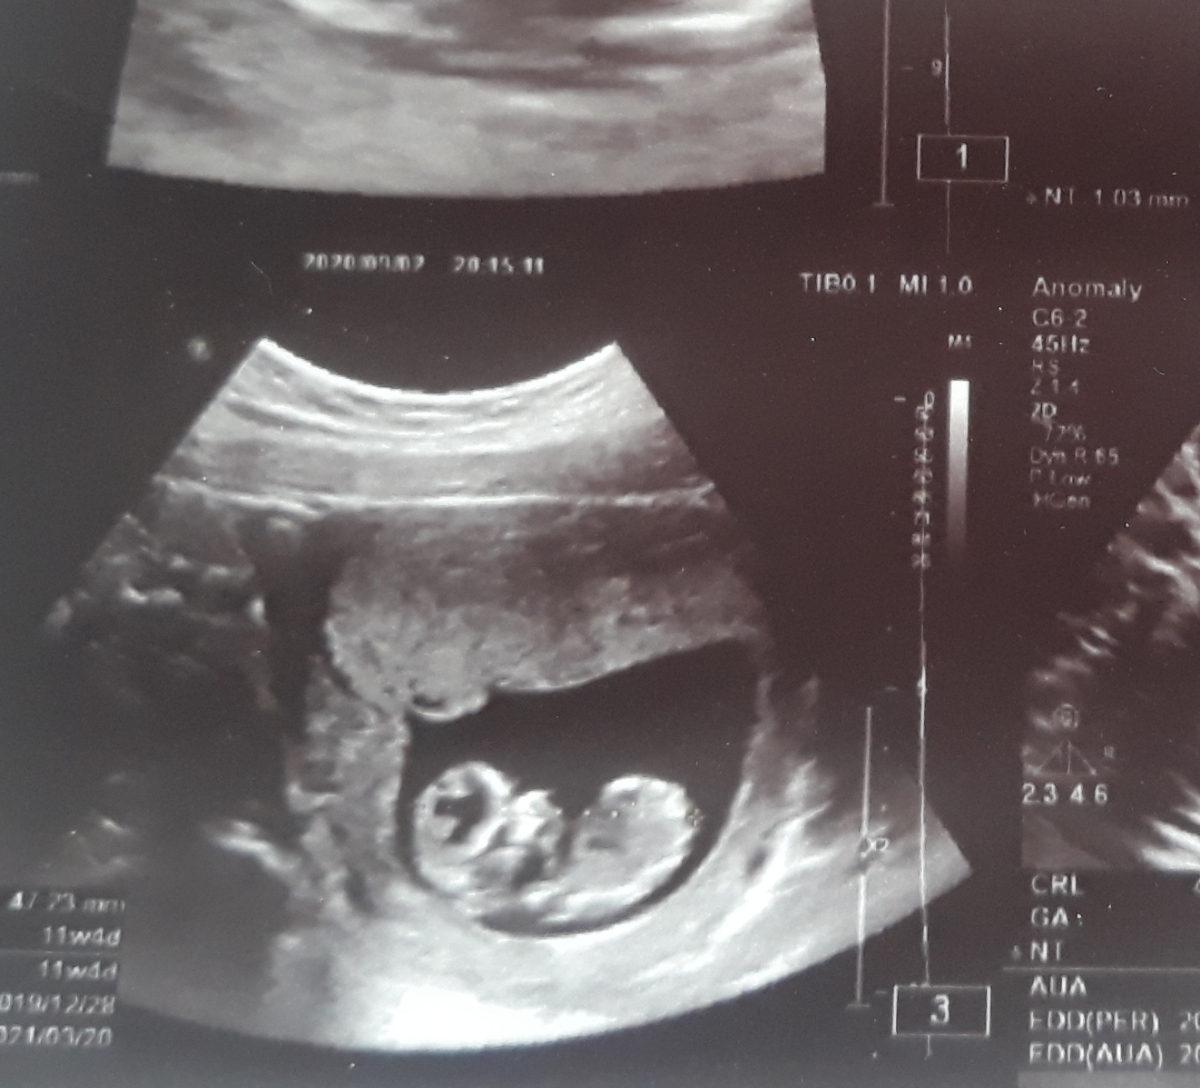

تشخیص بدید تحلیل کنین شانسی نگید تو رو خدا اگه ۵۰ ۵۰ بود هم بگین پنجاه پنجاهه میخوام در صد بگیرم از نظراتون ممنون مرسی

یه لحظه میفرستم چشم

دختر

پسر قوس کمر نداره دختر داره ینی کمرش گرده مثل سونو شما

البته دگ بازم حدسیات ماست

تو انومالی دقیق مشخص میشه

به نظر منم احتمالا دختر

75درصد میگم دختره😐

100درصد پسر

من میگم۷۰ درصد پسره از روی زاویه اون برآمدگی کوچولو با کمرش

۳۰ درصد دختر

حالا بمون توو خماری مثل من تا ۱۸ هفته جنسیت قطعیشو بفهمی😂😂😂😂

دخترههه عزیییزم.از ستون فقراتش مشخصه

من از روی جمجمه میگم دختره کله پسر کاملا گرده